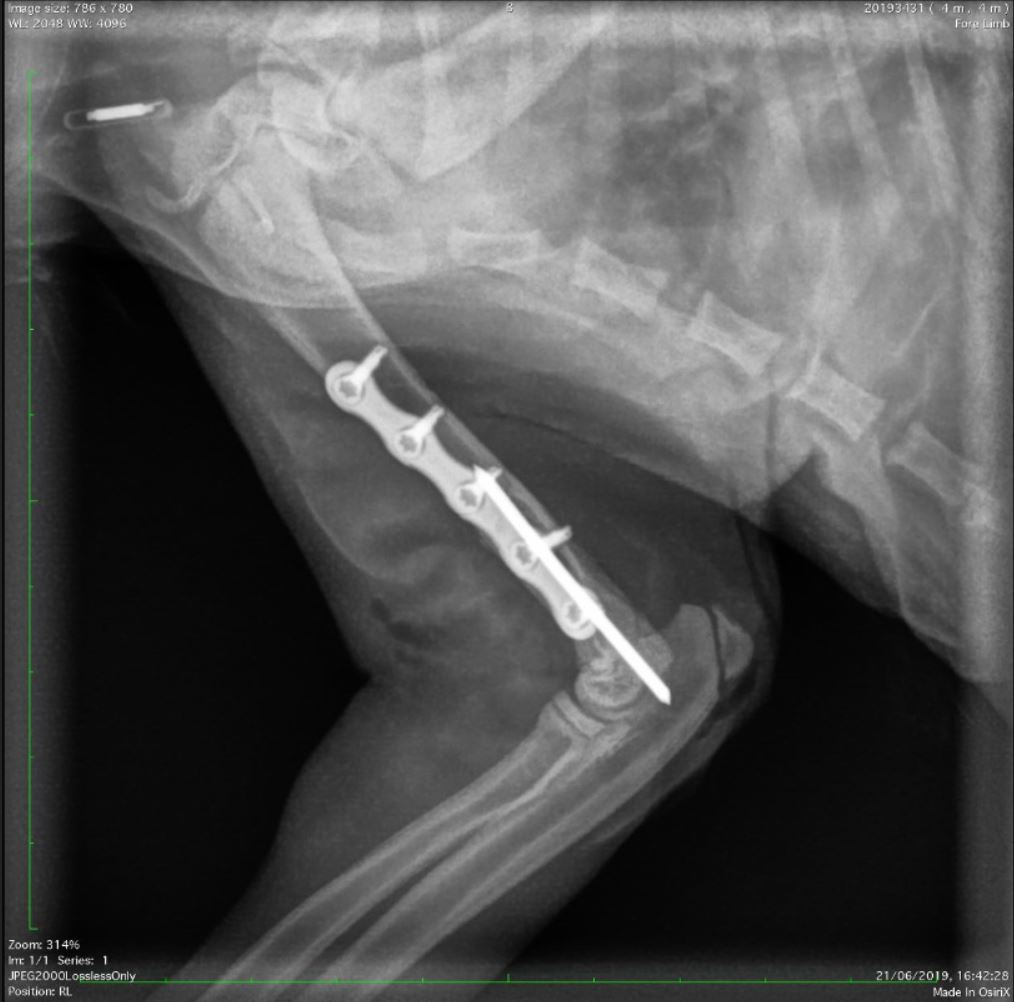

This course is designed for small animal practitioners seeking practical, effective methods to manage long bone fractures in dogs and cats. Participants will learn simplified techniques suitable for both straightforward and comminuted fractures, using modern implants that enhance surgical efficiency and reduce costs. By following key principles of fracture repair, complications can be minimized and outcomes improved.

Through a combination of lectures, clinical case discussions, and hands-on practice, attendees will gain confidence in choosing appropriate fixation methods and performing repairs. Practical sessions include fracture repair on plastic bone models and cadavers, followed by postoperative radiographs to assess technique and reinforce learning.

Apply the biomechanics of intramedullary pins, cerclage wires, bone screws, and plates, including compression, neutralization, and bridging methods